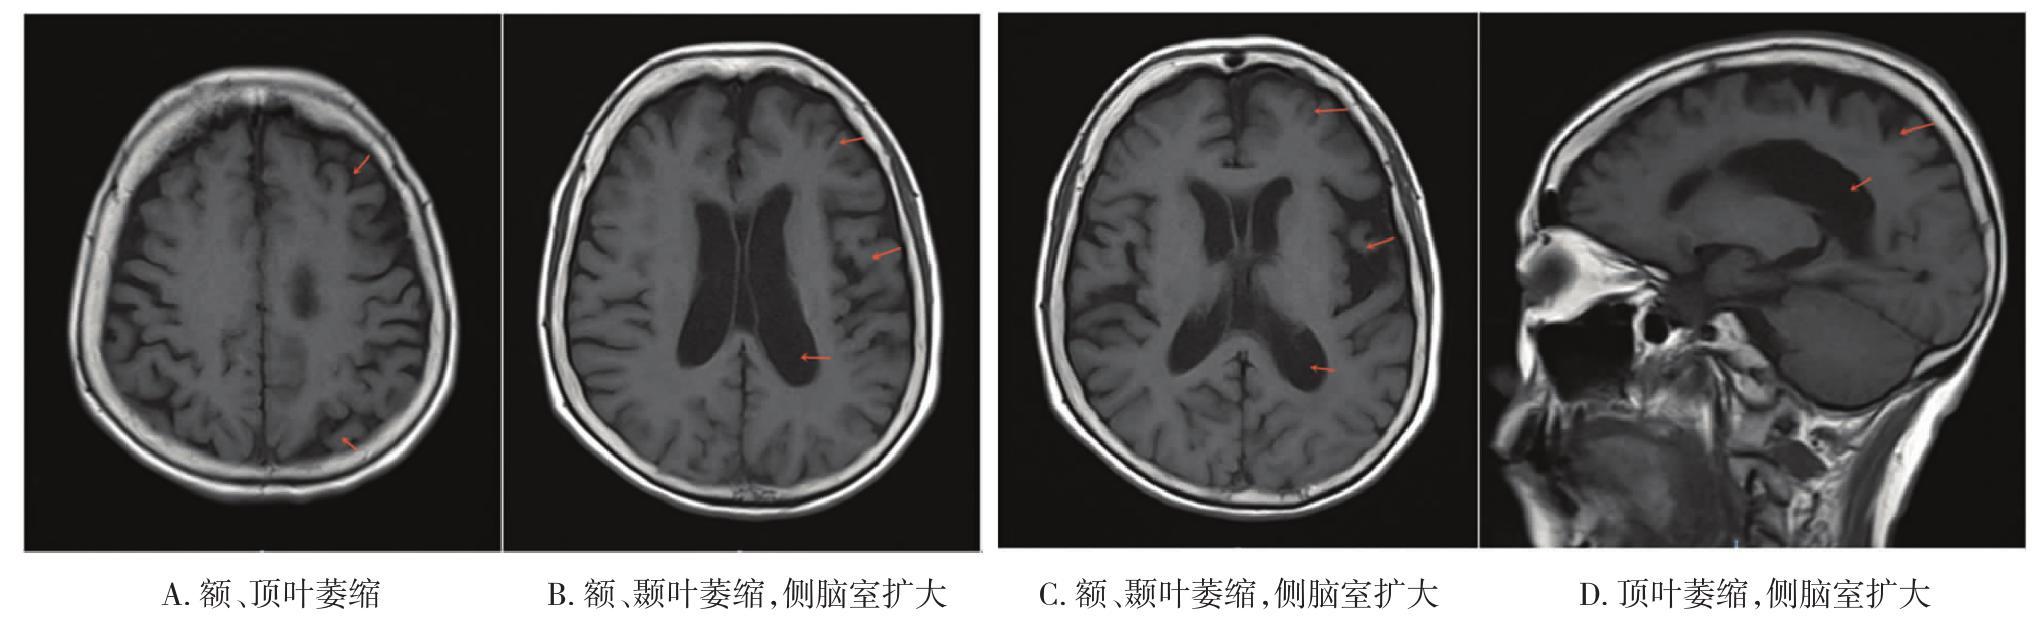

• 皮质基底节变性的影像诊断研究进展

2021, 46(7):818-822. DOI: 10.13406/j.cnki.cyxb.002866

摘要 (70) HTML (289) PDF 1.30 M (184) 评论 (0) 收藏

摘要:皮质基底节变性(corticobasal degeneration,CBD)是一种以不对称的运动症状和大脑皮质功能障碍为主要表现的神经退行性疾病。金标准为病理诊断,临床特征的异质性以及与其他神经退行性疾病在症状和病理方面的重叠性使得诊断难度大。现行诊断标准正确率较低,未将影像学纳入其中。本文主要综述近几十年CBD的影像学进展,包括计算机断层扫描(computed tomography,CT)、磁共振成像(magnetic resonance imaging,MRI)、放射性核素显像等,以及其在疾病鉴别方面的贡献。

• 0+1

• 1+1